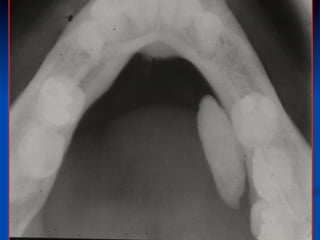

Diagnostics: Plain occlusal film

Effective for

intraductal stones,

while….

n  intraglandular,

radiolucent or

small stones may

be missed.